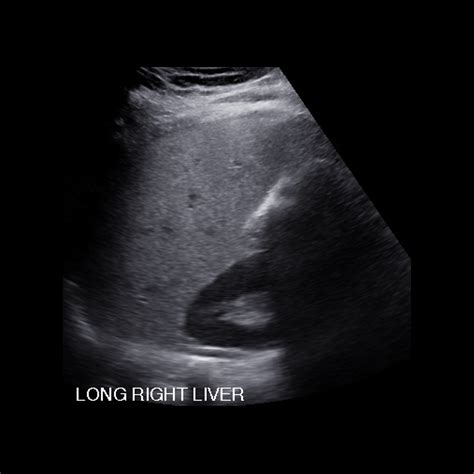

A liver ultrasound, also known as a hepatic sonogram, functions by emitting sound waves that bounce off internal structures. The transducer, a handheld device, captures these echoes and transforms them into visual representations on a monitor. Because the liver has a distinct texture, or "echogenicity," radiologists can quickly differentiate between healthy tissue and potential pathology.

When clinicians review liver ultrasound images, they look for changes in size, shape, and internal patterns. The consistency of the liver’s surface and the presence of any masses are critical markers for diagnosing conditions ranging from simple cysts to more complex oncological issues.

Also read: How Much Does Face Surgery Cost

During the procedure, the patient lies on their back or their side. The sonographer applies a water-based gel to the abdomen to ensure proper conduction of the sound waves. They will then move the transducer firmly across the upper right abdomen. Patients may be asked to hold their breath periodically to help the sonographer capture images while the liver is in a fixed position.